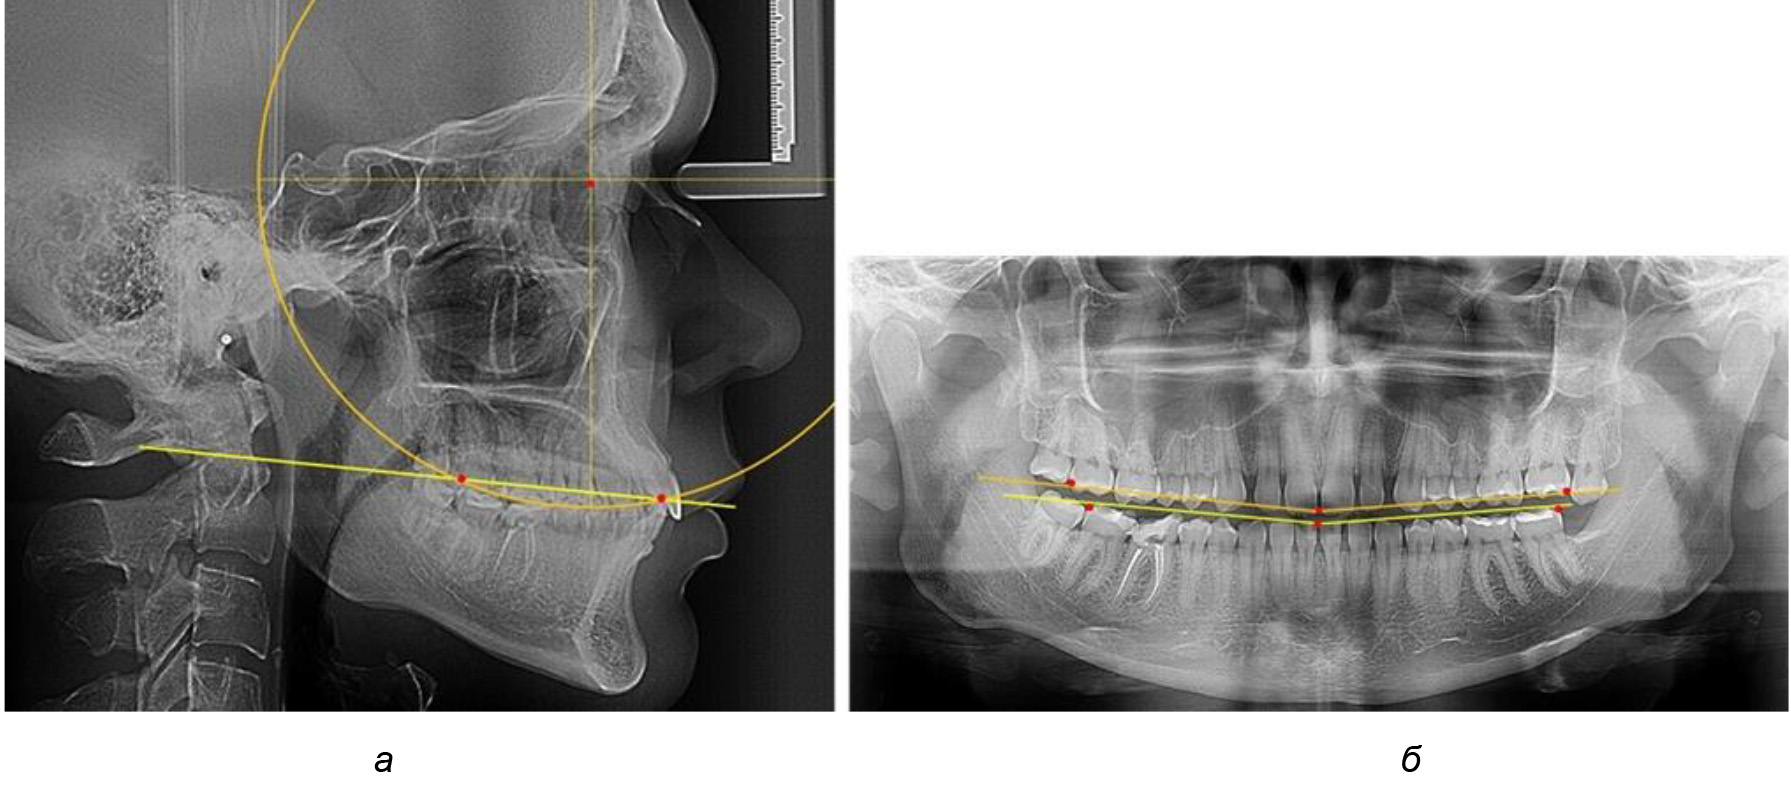

Рис. 2. Особенности кривой Spee на ТРГ (а) и ОПТГ (б) у людей с признаками вертикального роста

В ходе исследования установлено, что в 1-й подгруппу вошли ТРГ и ОПТГ 18 человек 1-й группы, что составило (29,03 ± 5,78) % от всех пациентов, рентгенограммы которых были проанализированы. У всех пациентов величина угла нижней челюсти была более 125° и в среднем составила (129,89 ± 3,62)° и характеризовала вертикальный тип нижней челюсти.

Учитывая существенную вариабельность линейных показателей, обусловленных типологическими (гнатическими и дентальными) вариантами зубочелюстных дуг, анализ проводили только при измерении глубины кривой Spee в наиболее углубленном месте и оценивали относительный показатель через отношение радиуса круга к сагиттальному расстоянию окклюзионной линии.

Анализ результатов показал, что глубина кривой Spee в среднем по подгруппе составил (4,12 ± 0,53) мм как при анализе ТРГ, так и ОПТГ.

Деление величины радиуса круга к длине окклюзионной линии составило 1,623 ± 0,02. Таким образом, для определения радиуса окружности, соответствующей кривизне окклюзионного контура боковой ТРГ, необходимо измерить расстояние между передней и задней окклюзионными точками и последующим умножением полученной величины на число Фибоначчи (рис. 2).

На рентгенограммах людей 2-й подгруппы (30 человек с нейтральным типом роста) величина угла нижней челюсти в среднем составила (120,34 ± 2,19) ° и характеризовала нейтральный тип нижней челюсти.

Глубина кривой Spee в среднем по 2-й подгруппе составил (3,54 ± 0,58) мм, что было незначительно меньше, чем при анализе аналогичного показателя 1-й подгруппы.

Достоверных различий с показателями, полученными при анализе ТРГ и ОПТГ, нами не отмечено (р ˃ 0,05). Деление величины радиуса круга к длине окклюзионной линии составило 1,612 ± 0,02, что, так же как и в 1-й подгруппе, было близким по значению к числу Фибоначчи (1, 618).

Рис. 3. Особенности кривой Spee на ТРГ (а) и ОПТГ (б) при нейтральном типе роста нижней челюсти